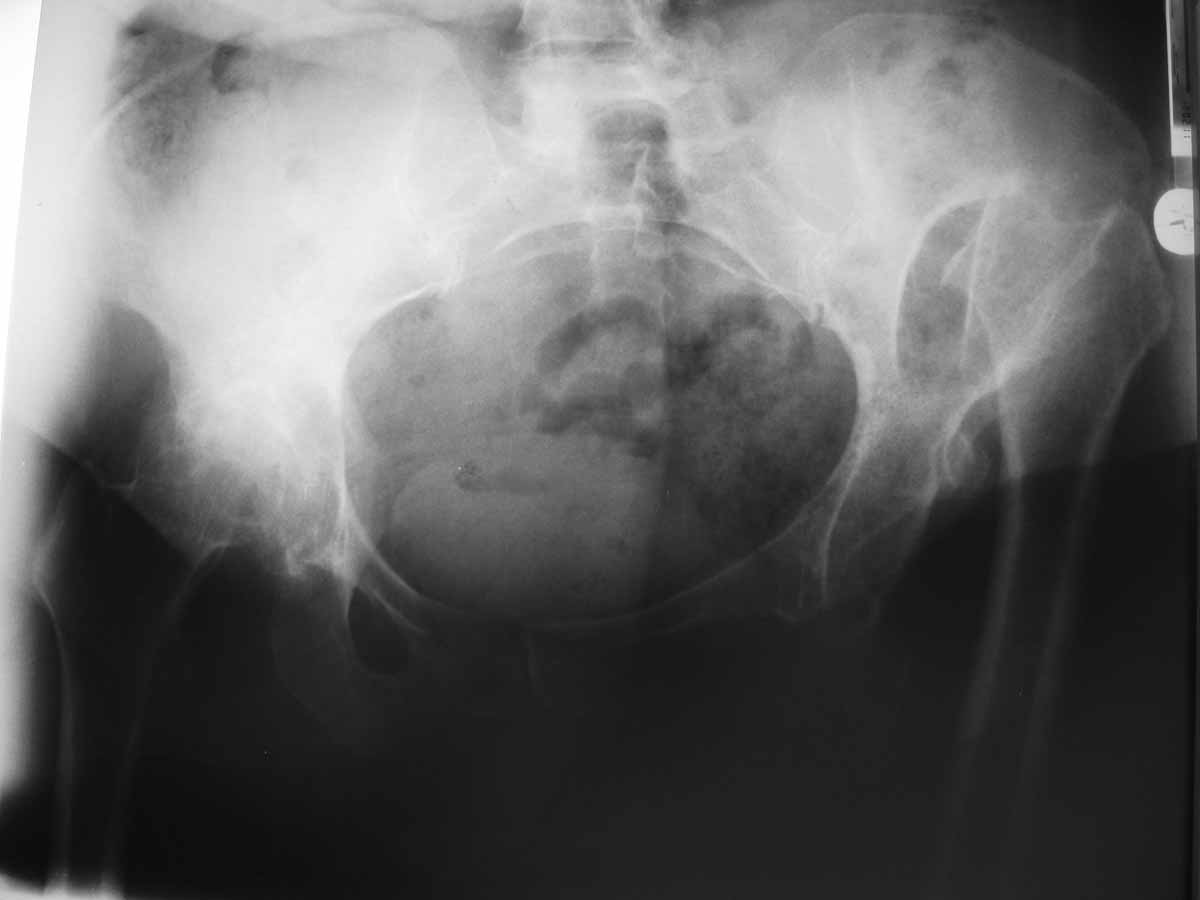

Доброго времени суток уважаемые коллеги, к нам поступила больная 58 лет с правосторонним неоартрозом, левосторонним анкилозом тазобедренного сустава, деформирующий гонартроз II-III степени с обеих сторон, укорочение правой нижней конечности на 5.7 см. Больная жалуется на боли в коленном и тазобедренном суставах слева. Больная сохранна, хотелось бы услышать мнения по тактике лечения больной.

В таких случаях мы выполняем последовательно двустороннее эндопротезирование. Если верить позиции на фото, то слева - высокий вывих бедра, а справа - анкилоз, но скорее всего это либо фиброзный анкилоз, либо просто выраженная контрактура.Слева показана укорачивающая остеотомия с имплантацией чашки в анатомическое положение. Предпочтение отдаем операции разработанной финским коллегой Paavilainen'ом, техника операции описана в нашей книжке. Операция технически непростая, но эффективная. Справа все проще, практически стандартная ситуация с небольшими нюансами.

Уважаемый Артак! Для определения тактики лечения, составления плана ортопедических мероприятий, хотелось бы увидеть Р-граммы позвоночника, обоих коленных суставов. Хотя бы Ваше описание патологии этих анатомических образований. Судя по представленной информации больную больную заставили обратиться боли слева. Причина их видится в перегрузке левой нижней конечности из за укорочения правой. Боли слева в тазобедренном суставе свидетельствуют и о том, что анкилоза нет.

Исходя из этого видимо целесообразно выполнить вначале эндопротезирование левого тазобедренного сустава, затем разобраться с левым коленом (требуется ли эндопротезирование, и если да то выполнить его). Затем эдопротезирование правого тазобедренного.

Уважаемый Артак! Справа особых прблем для протезирования не предвидется, а слева возможно низведение проксимального отдела бедренной кости в теч. 2-х недель до уровня вертл. впадины при пом. АВФ с последующим ТЭП ТБС. Укорачивающая остеотомия по Паулайнен (см. рекомендации Р.М. Тихилова) может привести к разнице в длине конечностей после двустороннего ЭП. АИФ

Одномоментное удлинение при укорачивающей остеотомии составляет около 3,5-4 см при условии, если раньше пациент не был оперирован. Если ранее выполнялась операция, то удлинение составит максимум 3 см. Любое предшествующее удлинение, в том числе АВФ ограничено седалищным нервом и составляет 5 см не более. Вот теперь и прикиньте, стоит ли мучить себя и пациента ради 1 см.